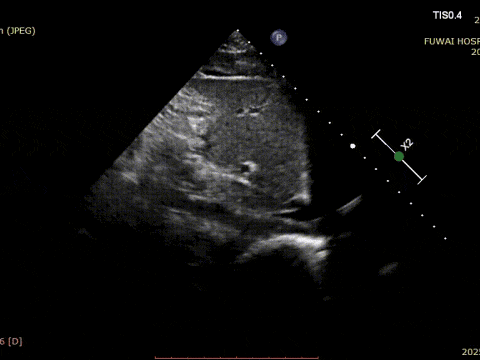

1. The ASD was central in location, with a measured diameter of approximately 8.1 mm (bicaval view) and 8.2 mm (aortic short-axis view).

The procedure was guided by TTE following the PAN procedure developed at Fuwai Hospital. This radiation-free, real-time imaging technique offers high-resolution anatomical visualization, ensuring accurate device placement and minimizing complications—particularly valuable in young, reproductive-age patients.